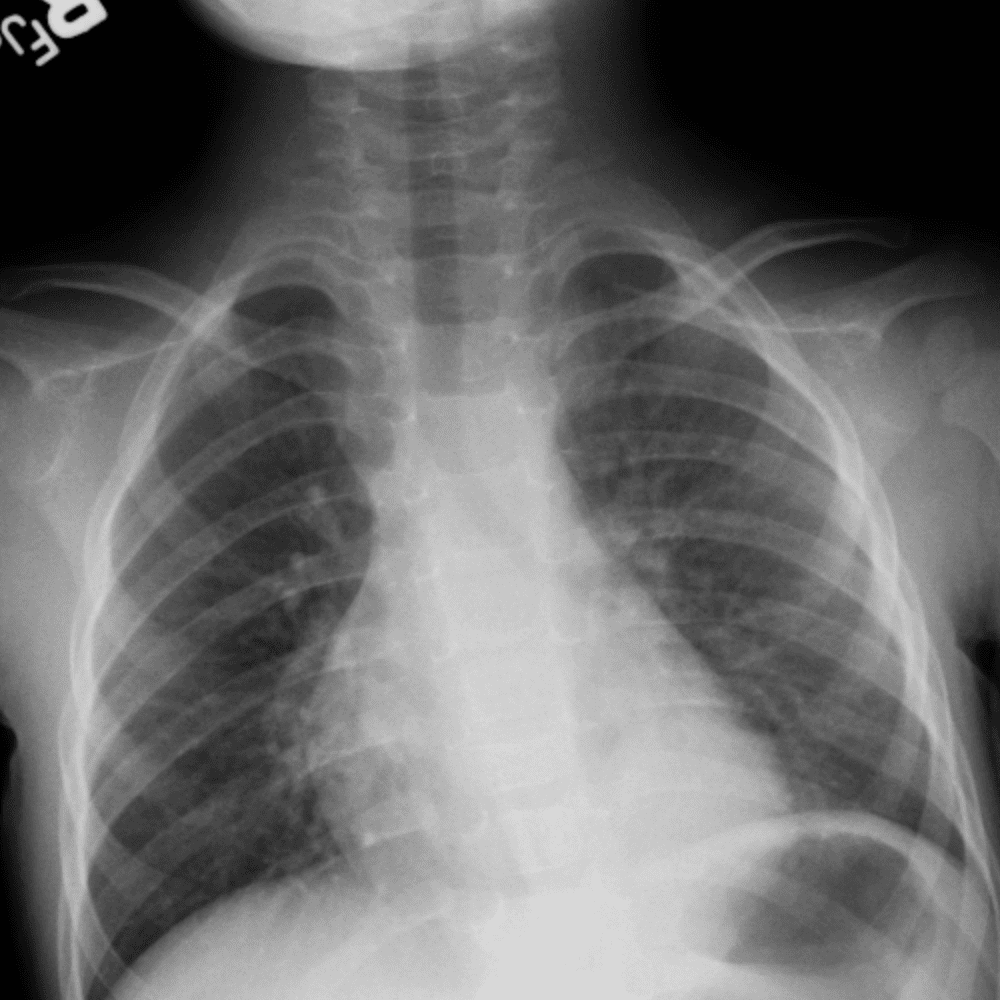

Peds Chest

Practice

Simulates call by including subtle or difficult cases and some normals.

50 cases